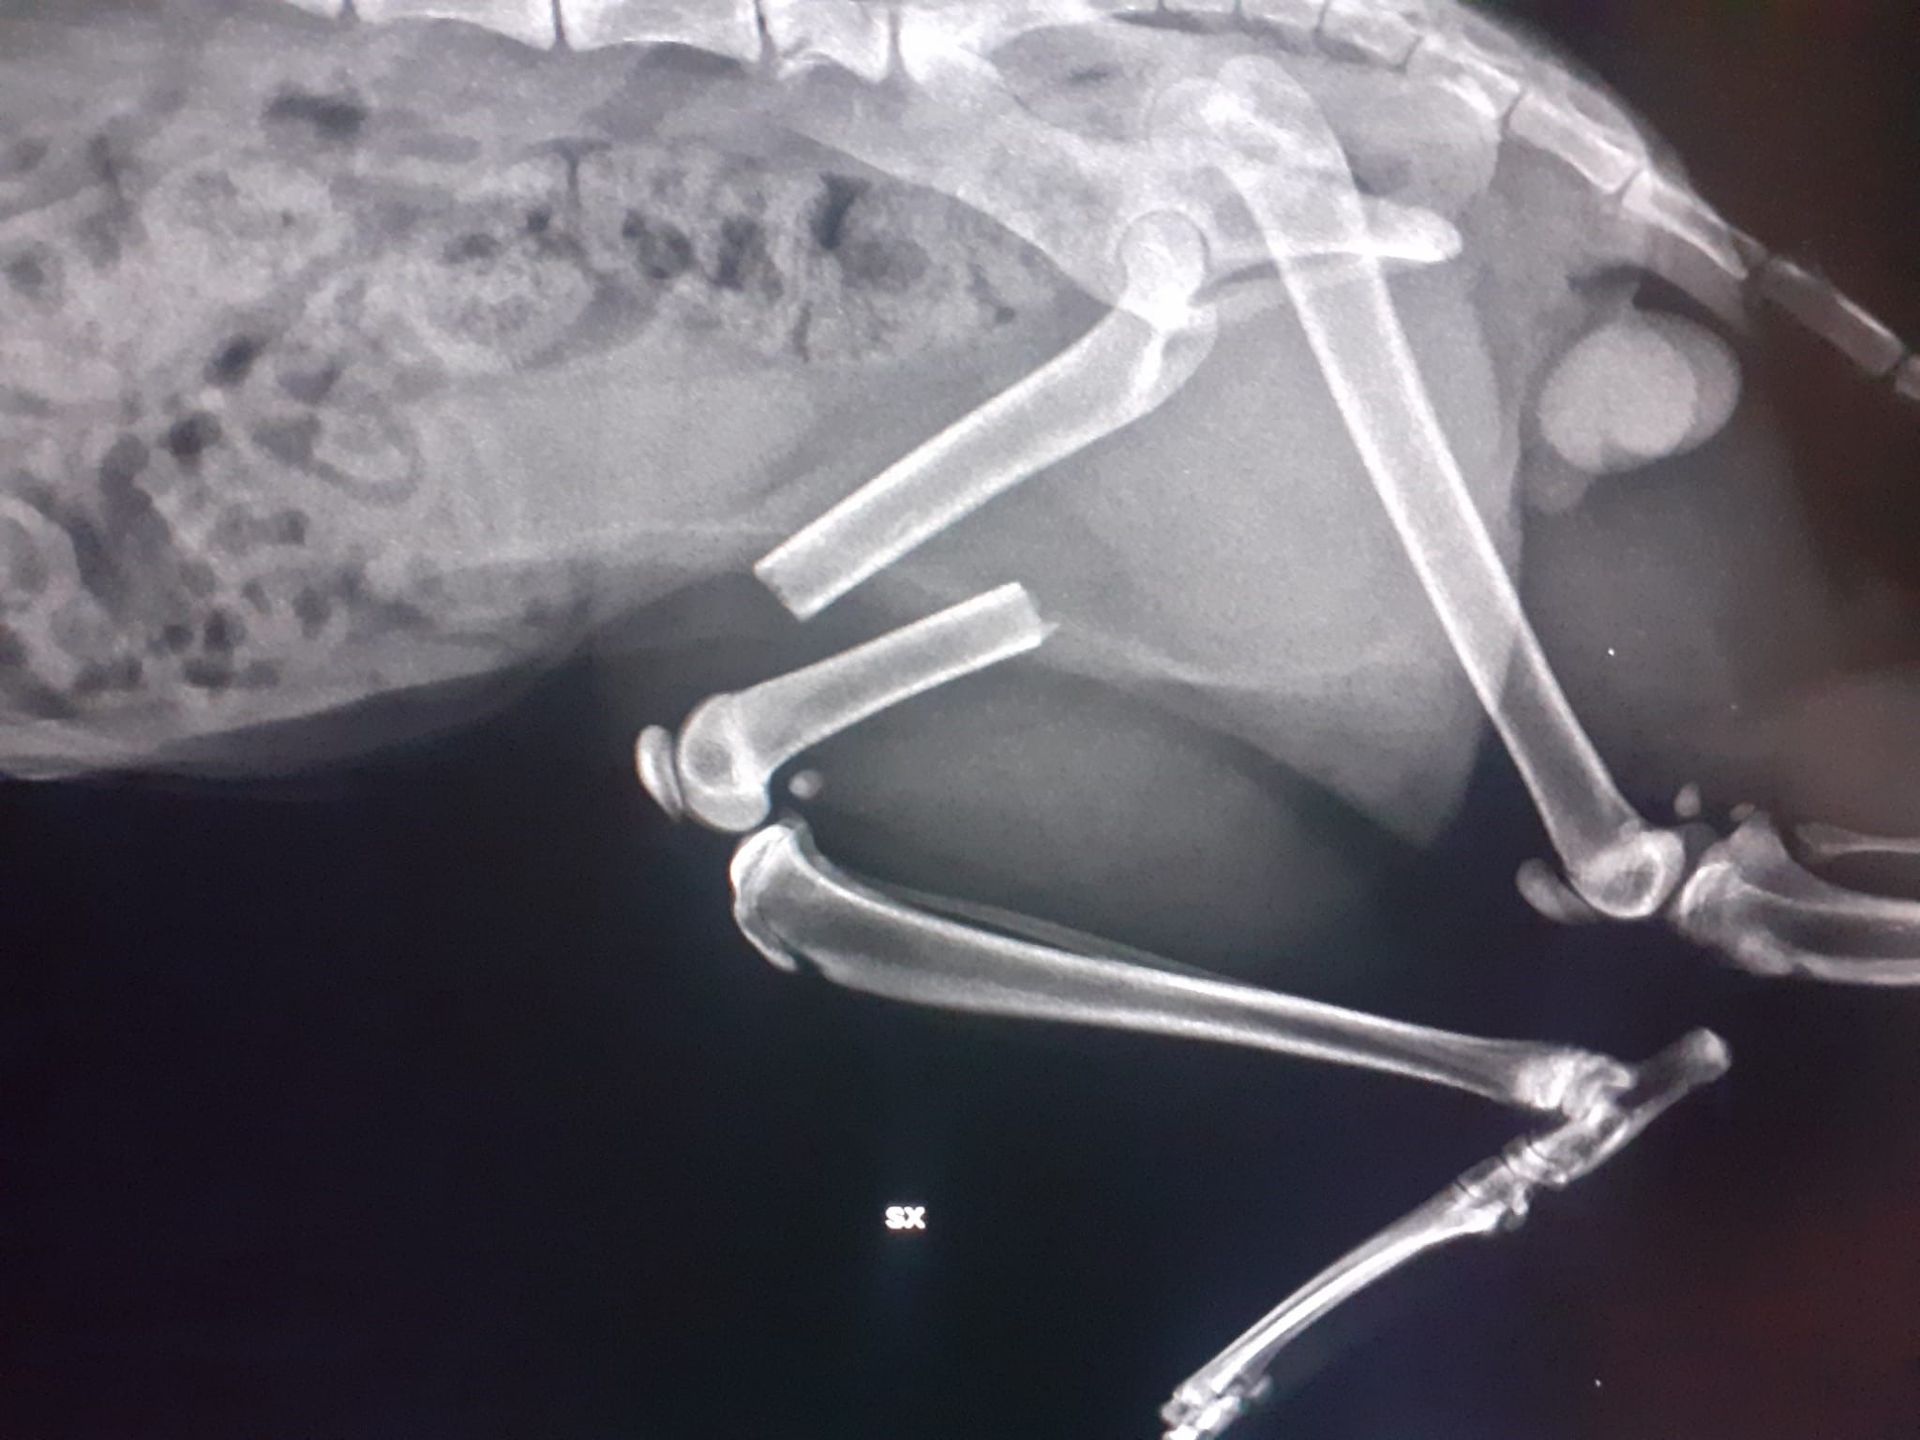

Alla clinica veterinaria Città di Catanzaro siamo a disposizione per eseguire controlli radiografici specifici per la diagnosi di alcune tra le più diffuse malattie ortopediche che affliggono molte razze canine, soprattutto nella fase della crescita.

Con sicurezza ed efficacia, i nostri esperti di ortopedia veterinaria sono capaci di prevenire e curare tutti i tipi di problematiche relative all'apparato muscolo scheletrico, come la displasia dell’anca e del gomito.

In più, la nostra équipe si compone di esperti traumatologi che si dedicano alla diagnosi, al trattamento e alla prevenzione di un ampio spettro di patologie dell'apparato locomotore.

Infine, grazie alla chirurgia ortopedica, è possibile velocizzare la guarigione di tutti quegli animali che hanno subito fratture ossee in seguito a qualsiasi tipologia di incidente.